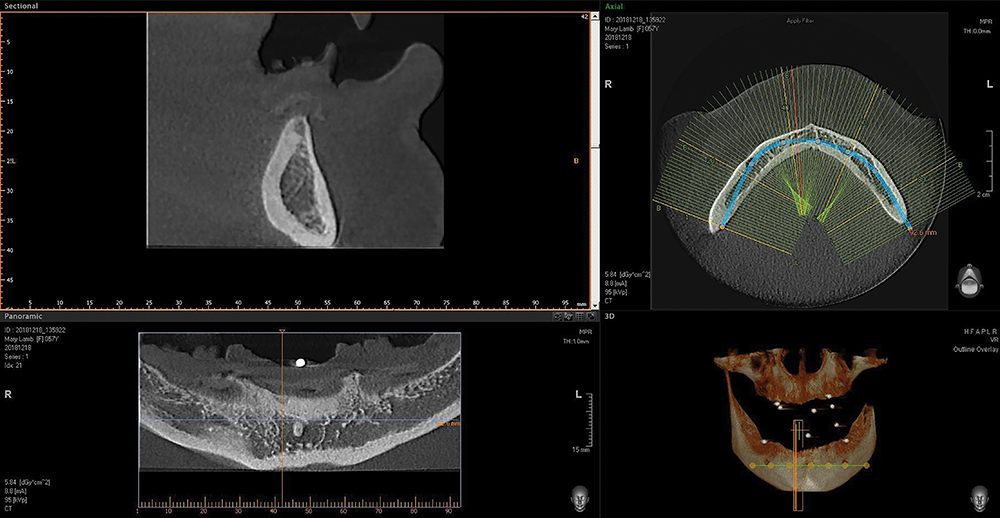

Our patient is a middle-aged female who presented with a chief complaint of ill-fitting, unstable maxillary and mandibular conventional dentures. We discussed several options, including relining her existing dentures, fabrication of new conventional dentures, implant-retained overdentures and fixed implant-supported prostheses. The patient opted for implant placement and restoration with a Locator Overdenture — which would provide an effective, economical means of addressing the patient’s needs and improving prosthetic stability and dental function.